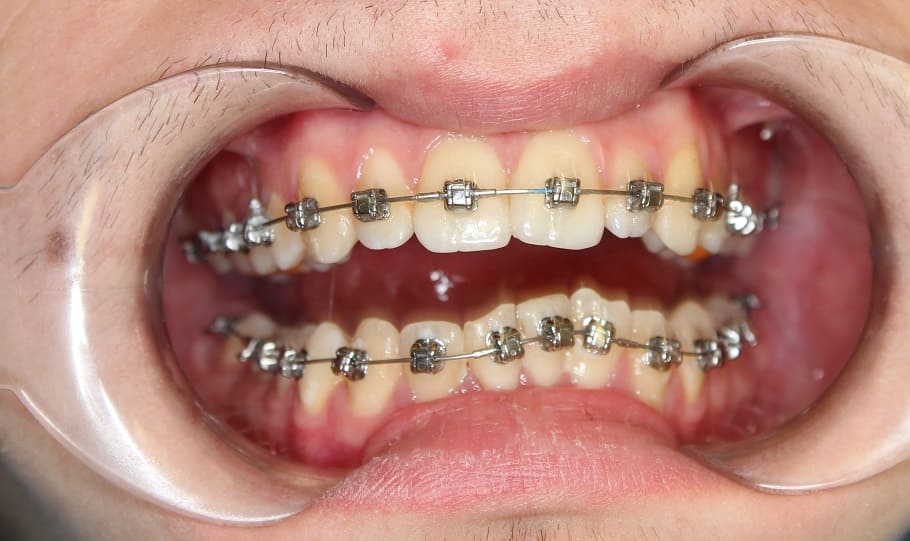

Лечение на самолигирующей брекет-системе Н4. Ортодонтическое лечение заняло 2 года.